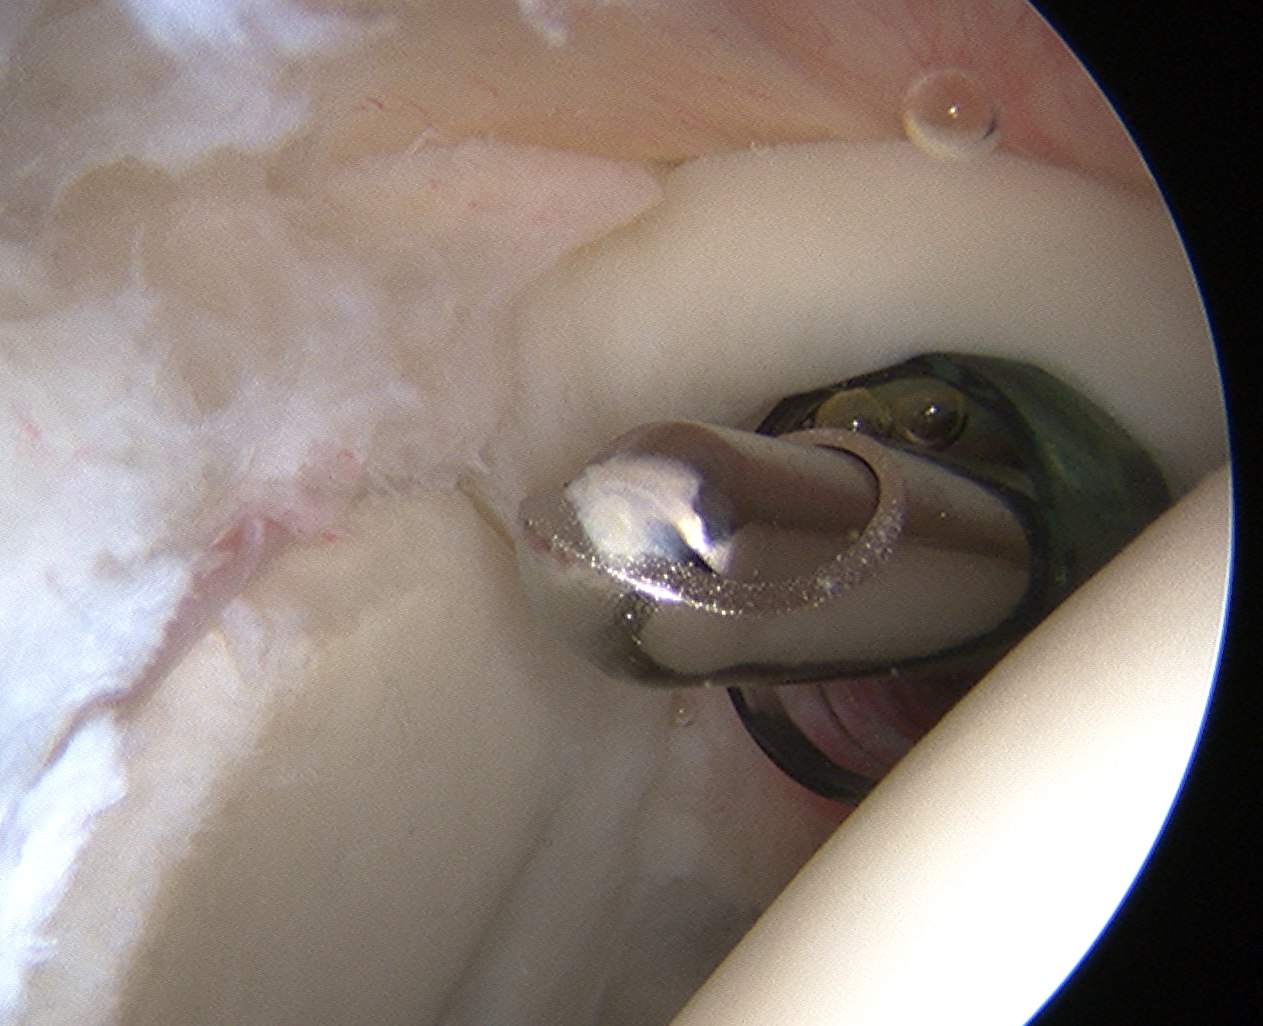

Subacromial space

Portals

| Posterior | Lateral subacromial portal |

|---|---|

|

Redirect posterior portal Under acromion |

Midportal clavicle |

| Usually viewing portal |

Rotator cuff repair / Subacromial decompression Distal clavicle resection |

![]() |